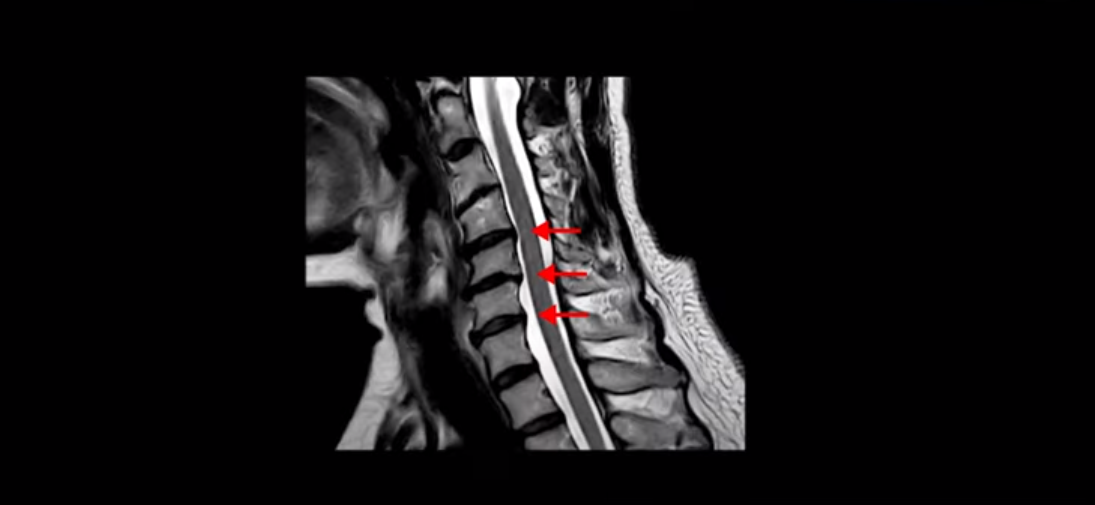

MRI에서도 보시다시피 여러 마디에 퇴행성 디스크가 있습니다.

이런 걸 협착이라고 부르는 거죠. 이 분의 가장 불편한 증상은 20년간 아픈 만성적인 목통증과 어깨통증, 두통과 눈 통증인데 최근 들어 가증 불편한 증상은 목이 아예 돌아가지 않는 겁니다. 그래서 운전할 때도 사이드 미러를 보려면 몸을 돌리셨다고 하는데요. 주사 효과도 전혀 없고 대학병원에서도 디스크와 협착인데 그냥 약먹고 운동만 하라고 하면 이 환자는 어떻게 해야 할까요?

이 환자분도 아까 X-ray에서 보여드렸듯이 아주 심한 일자목, 거북목이 있고 그 결과로 목의 거의 모든 마디가 다 퇴행이 진행되어 있죠. 즉 거북목은 모든 목질환, 특히 목디스크, 목협착증의 어머니 질환이며 그래서 목디스크를 치료하기 위해서는 반드시 거북목 때문에 짧아지고 뭉치고 굳고 뒤틀린 목 주변 근육들을 잘 치료해줘야 합니다.